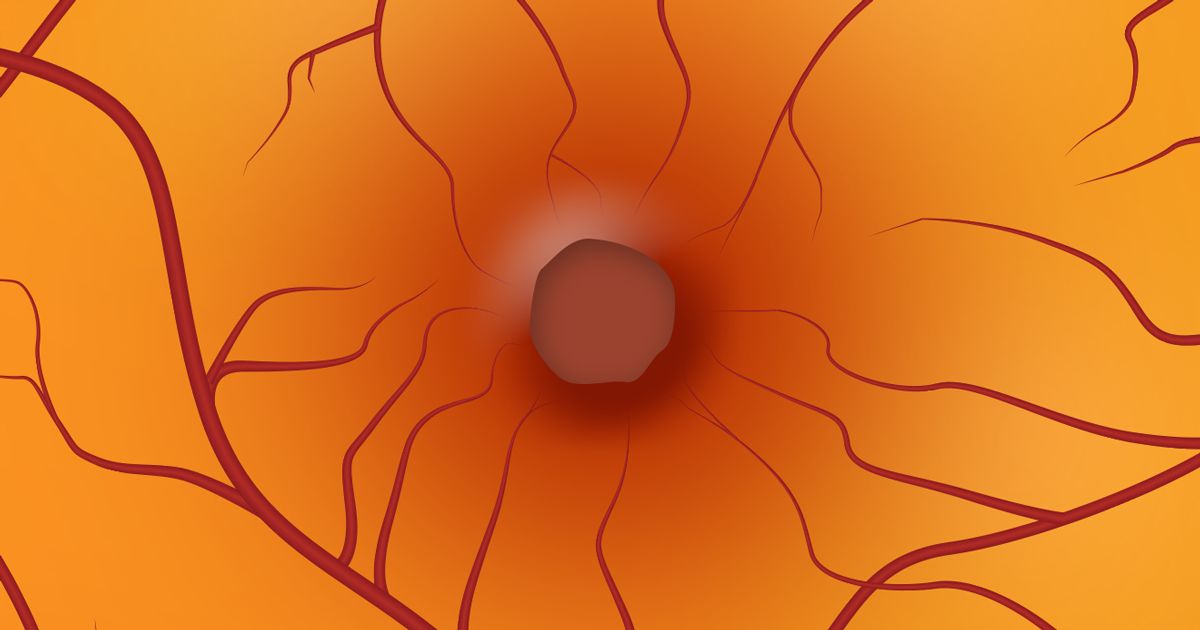

A mácula (ou mácula lútea) é uma região muito pequena no centro da retina. Visualmente, é a parte mais sensível da retina. A mácula é responsável pela acuidade visual, visão central detalhada (para ler, dirigir e reconhecer rostos, por exemplo) e visão de cores.

A mácula é cheia de células sensíveis à luz chamadas cones. O resto da retina é constituído principalmente por células fotossensíveis chamados bastonetes. Eles "enxergam" tons de cinza e preto, detectam movimentos e são responsáveis pela visão periférica.

Um buraco macular é uma pequena ruptura na mácula, que causa visão central embaçada e distorcida e que normalmente ocorre de repente.

Como o vítreo está ligado à retina com minúsculos filamentos de colágeno (uma proteína comum no corpo), esses filamentos de colágeno podem puxar a retina conforme o vítreo se liquefaz. Às vezes, isso pode rasgar um pequeno pedaço da retina, causando um buraco. Se esse pedaço de retina ausente estiver na mácula, é chamado de buraco macular.

Outra maneira pela qual os buracos maculares podem ocorrer devido a alterações no vítreo é quando os filamentos de colágeno dentro do vítreo permanecem presos à retina e se separam do vítreo líquido. Esses fios podem se contrair ao redor da mácula, fazendo com que ela desenvolva um buraco devido à tração.